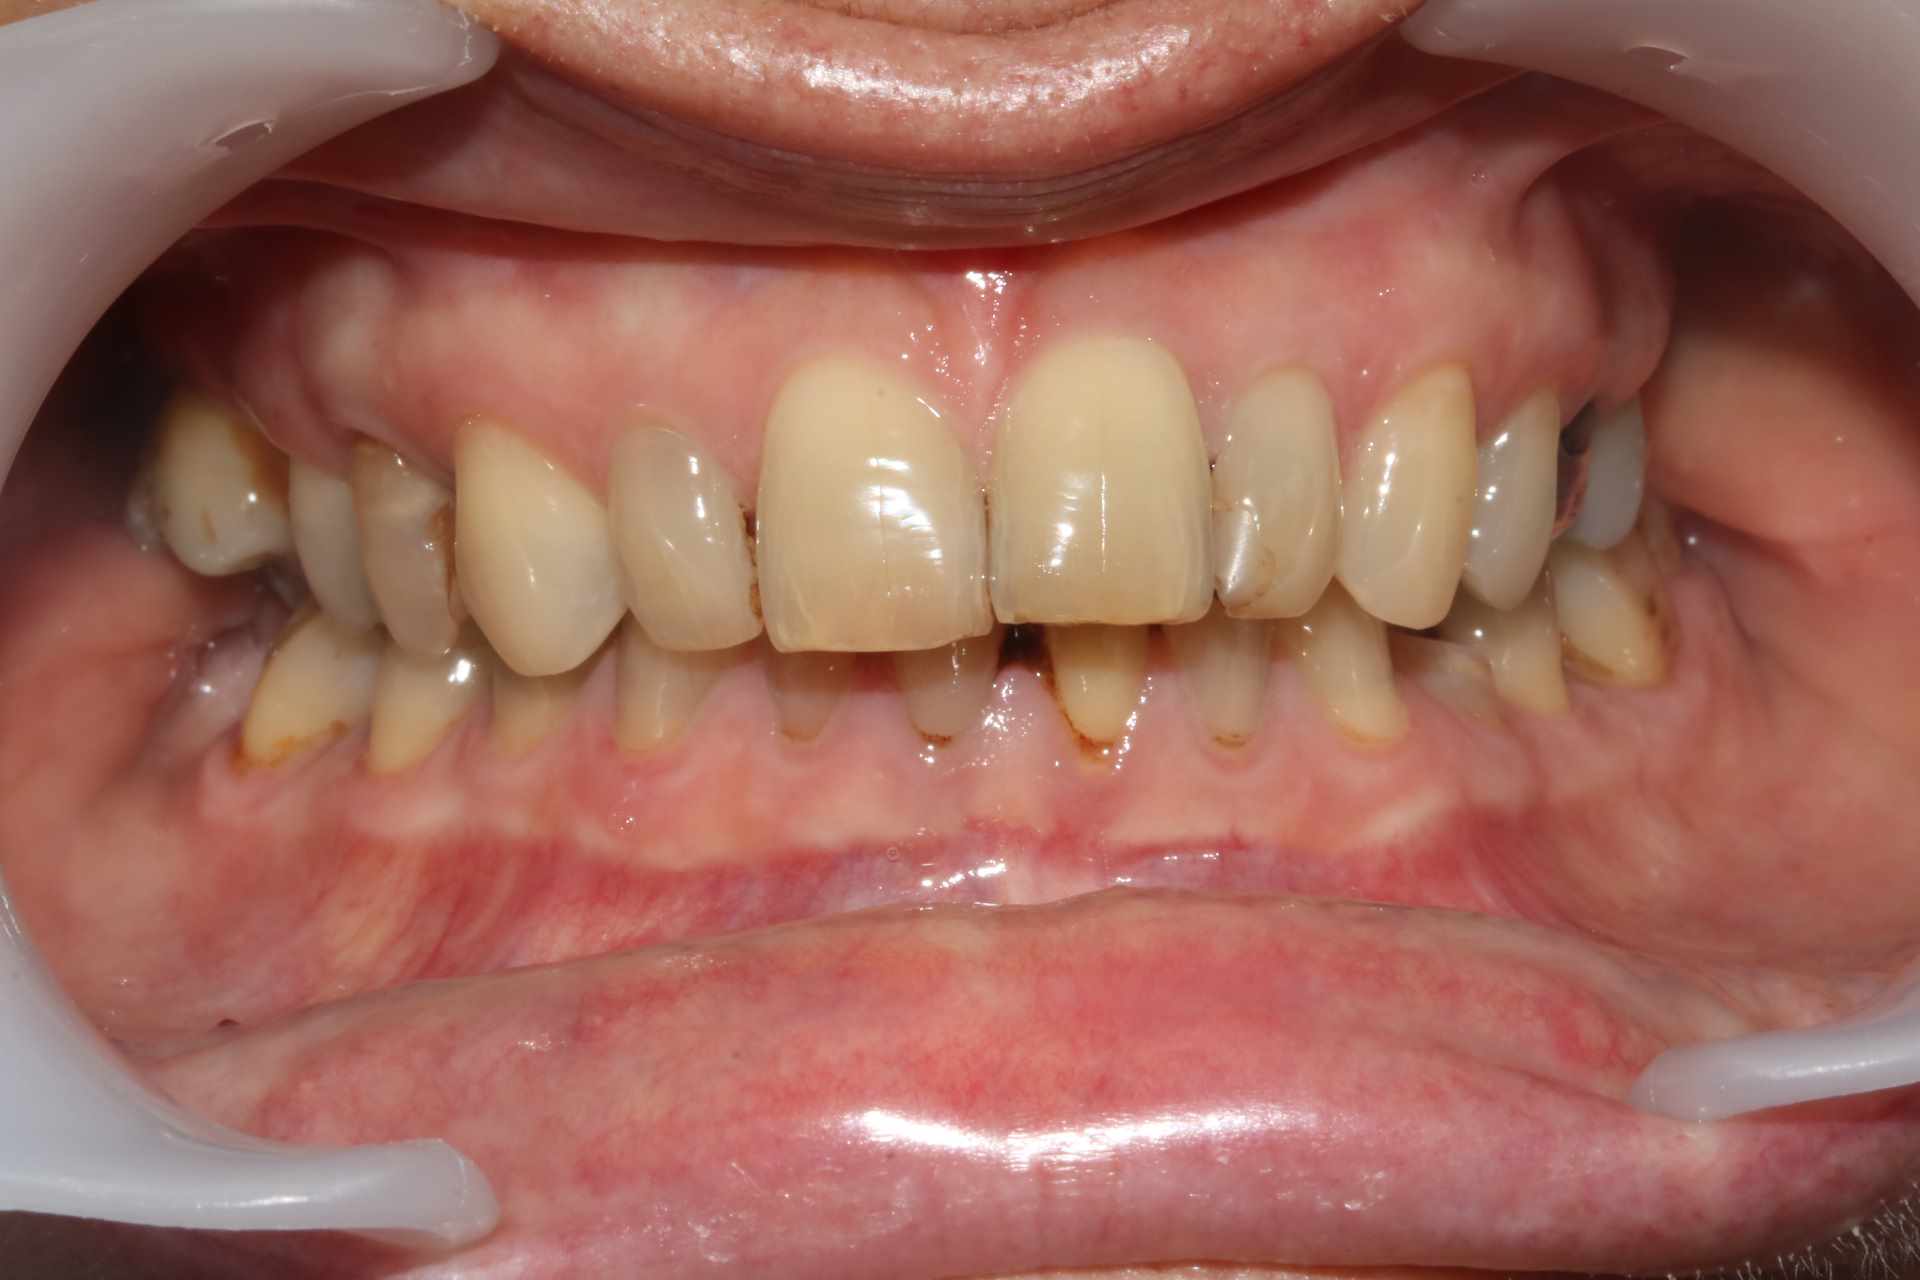

La patiente vient pour sa 34 fracturée ... mais n'a aucun calage molaire S 1. Je voudrais bien commencer par le calage postérieur mais j'aimerais les avis des implantos, manque de distance MD, proximité du sinus. Pas idéal non ?

Sinon... forte supra, mandibule en arrière.

Je dirais que la dame serre les dents mais que à priori elle grince pas trop trop au vu des abrasions visibles.

Ce qui me chagrinerait le plus c’est la mésio-version de la 47 suite au non remplacement de la 46 si je me trompe pas. Ça et la classe II. Sont toujours chiants les classe II.